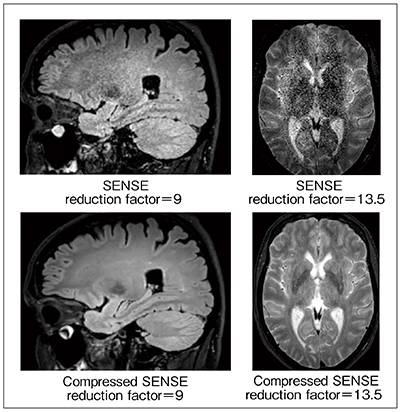

1.情報劣化を抑えた“Optimized Variable-density Sampling”

図2 SENSEとCompressed SENSEの画像の比較